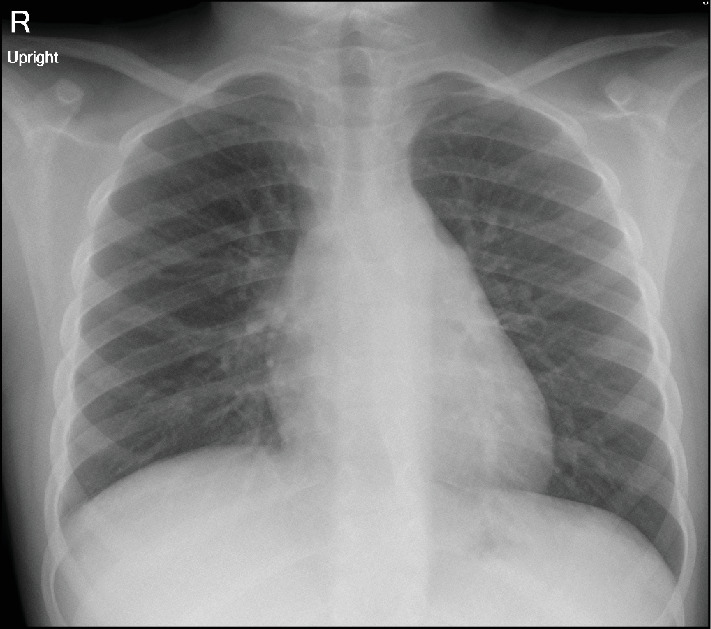

家族性地中海热(FMF)和克罗恩病(CD)是两种具有相似临床和生物学特征的慢性自身炎症性疾病。这两种疾病的特点都是慢性和复发性症状。在某些情况下,FMF可以与乳糜泻共存,这使得诊断和治疗具有挑战性。病例介绍:一名9岁的埃及儿童在5岁时根据临床症状和内窥镜组织病理学检查结果被诊断为乳糜泻。最初,患者对生物治疗(抗tnf α)反应良好,症状改善,炎症标志物和粪便钙保护蛋白水平下降。7岁时,患儿开始出现频繁发热并伴有胸膜炎性胸痛。多次胸部x光检查发现右侧胸腔积液。由于免疫抑制,患者被诊断为复发性急性细菌性肺炎,并接受了多个疗程的口服抗生素治疗。在最后一次报告中,在其中一次发作中,由于对抗生素缺乏反应,持续升高的炎症标志物(CRP, ESR)和无法解决的轻度右侧胸腔积液,因此进行了进一步的调查。根据患者的临床表现和胸部影像学,怀疑为FMF。详细的家族史显示,一位一级表亲有FMF阳性诊断。进行基因检测,发现两个杂合致病突变,支持FMF诊断。秋水仙碱治疗可防止进一步发作。患者继续接受胃肠道小组对CD的随访护理,并维持阿达木单抗。结论:对于表现出肺部症状且对乳糜泻治疗无反应的乳糜泻患儿,应考虑FMF。

Introduction: Familial Mediterranean fever (FMF) and Crohn's disease (CD) are chronic autoinflammatory disorders that share similar clinical and biological features. Both disorders are characterized by chronic and relapsing symptoms. In some cases, FMF can coexist with CD, which makes diagnosis and treatment challenging. Case Presentation: A 9-year-old Egyptian child was diagnosed with CD at the age of 5, based on clinical symptoms and endoscopic histopathologic findings. Initially, the patient responded well to biological therapy (anti-TNFα), showing improvements in symptoms along with declines in inflammatory markers and fecal calprotectin levels. At the age of 7, the child began experiencing frequent episodes of fever accompanied by pleuritic chest pain. Right-sided pleural effusion was identified on repeated chest X-rays. The patient was diagnosed with recurrent acute bacterial pneumonia due to immune suppression and was managed with multiple courses of oral antibiotics. During the last presentation, in one of these episodes, further investigation was pursued due to a lack of response to antibiotics, indicated by persistently elevated inflammatory markers (CRP, ESR) and nonresolving mild right-sided pleural effusion. FMF was suspected based on the patient's clinical presentation and chest imaging. A detailed family history revealed a positive FMF diagnosis in a first-degree cousin. Genetic testing was performed, which revealed two heterozygous pathogenic mutations that support the FMF diagnosis. Treatment with colchicine prevented further episodes. The patient continued to receive follow-up care from the GI team for CD and was maintained on adalimumab. Conclusions: FMF should be considered for children with CD who exhibit pulmonary symptoms that do not respond to CD treatment.